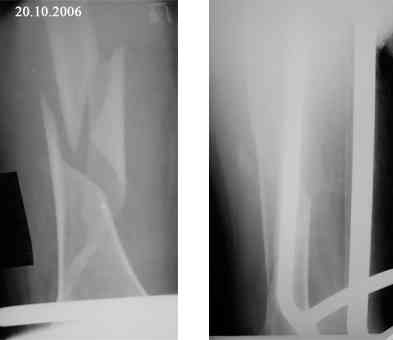

В продолжение темы оскольчатого перелома бедренной кости.

Р-граммы в динамике

Уважаемый Александр! Спасибо за предложение по устройству больной. Каким образом вы могли бы помочь я не вижу. Больная из г. Евпатории Крым, Украина, как я уже писал неимущая. В нашем отделении такие операции не делаются (хотя есть ЭОП - единственный в Крыму). Заведующий на оперативное лечение больной почему-то не настроен. По-моему несращение ей обеспечено, завтра зайду к ней - проверю (52 дня на вытяжении!). Вопрос - что с ней делать дальше если на операцию не идут? Выгнать с ложным суставом домой умирать? Или лежать до самой смерти (близкой) на вытяжении - я понимаю - человек ко всему привыкает но не до такой же степени. Кстати - сопутствующее у нее сросшийся чрезнадмыщелковый перелом левой плечевой кости (травма и операция (открытая репозиция, МОС спицами) в мае 2006 года).

Чудеса какие то. Уважаемый Антон. Поскольку зав. отделением сказал нет оперативному лечению,значит тема закрыты. Более того. Таким образом он взял ответственность за судьбу пациента на себя. То есть в определенной степени ваша совесть чиста. Лет 20 назад мы тоже лечили некоторых больных таким же методом. Что можно посоветовать в данном случае. 52 дня на вытяжении - это круто.Если клинически имеются какието признаки консолидации - отсутствие подвижности или тугоподвижность в области перелома- то есть нет угрозы вторичного смещения, накладывайте кокситную гипсовую повязку и выписывайте пациента. Может это поможет, или пациет будет искать другую болницу. Если сохраняется выраженая подвижность в области перелома - консолидация сомнительна при консервативном лечении.